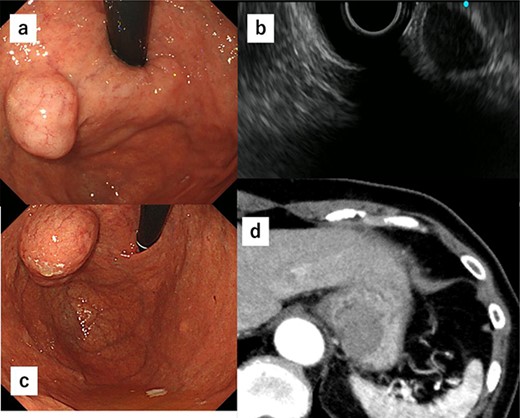

Due to the tumor location, performing conventional laparoscopic surgery to achieve local resection with sutures that do not damage the EGJ and prevent gastric stricture was difficult. We performed robot-assisted laparoscopic surgery combined with endoscopy to determine the minimum excision margins. Five trocars were placed in the anterior abdomen, guided by a horizontal reference line 8 cm cephalad to the umbilicus. An 8-mm port was inserted into the umbilicus, and another 8-mm port was inserted on the left side of the abdomen. A 12-mm port for use by the assistant was placed between the latter port and the umbilicus. Similarly, an 8-mm port was inserted on the right side of the abdomen, and a 12-mm port was placed between that port and the umbilicus. Our robot-assisted gastrectomy was regularly performed using the DBM, with Maryland- and fenestrated bipolar forceps in the right- and left hand, respectively. We opened the omental bursa, and the anterior wall of the stomach was sufficiently mobilized to confirm the tumor location. After mobilization, another tumor, which looked like a lymph node, was identified and resected (Fig. 2a). Upper endoscopy revealed the tumor, and the wedge was pushed using biopsy forceps; in this manner, we confirmed the minimum resection line (Fig. 2b). The laparoscopic and endoscopic views were displayed on the same monitor so that the surgeon could confirm the position of the biopsy forceps in real time. Minimum partial resection was performed using Maryland bipolar forceps according to the line confirmed from inside and outside the stomach (Fig. 2c). Reconstruction was performed using Albert–Lembert sutures (Fig. 2d). The specimens were retrieved using an endobag, and a drain was placed under the stomach. The operative time was 158 min, and blood loss was 1 mL. The postoperative course revealed no adverse events, and the patient was discharged on postoperative day 6.

(a) After mobilization of the gastric posterior wall, another tumor, which looked like a lymph node, was identified and resected. (b) Upper endoscopy shows the tumor and the wedge pushed using biopsy forceps; in this manner, we confirmed the minimum resection line. (c) The minimum partial resection was performed using Maryland bipolar forceps according to the line confirmed from inside and outside the stomach. (d) Reconstruction was performed using Albert–Lembert sutures.